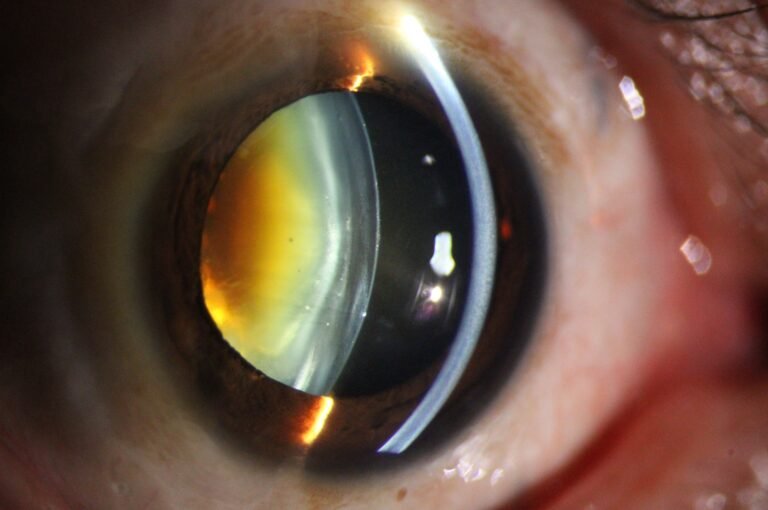

Precision Optics

Premium Optical System

High-resolution visualization across a wide range of magnifications. Multi-coated optics deliver distortion-free anterior segment imaging for confident clinical assessment.

- 5 Step Magnification: 6×, 10×, 16×, 25×, 40×

- 24 Megapixel SLR Camera

- Automatic Digital Optimization

- Automatic Eye Position Recognition for Digital Acquisition